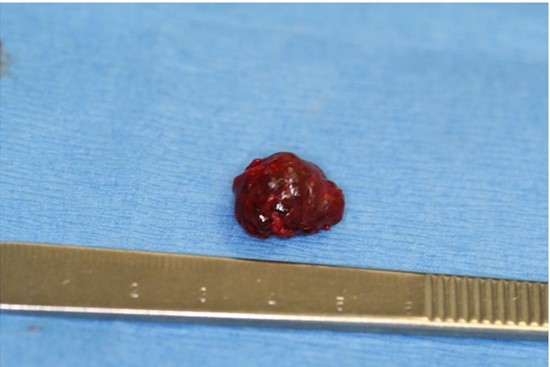

A 73-year old Asian female presented to the office for evaluation of a mass on the left cheek (Figure 1). Medical history reported by the patient included hypertension and osteoporosis. Medications included Losartan 50mg daily and Alendronate 70mg once per week. The patient stated that the mass appeared to be enlarging in size and was noticeable to her family. She denied pain or tenderness in the area of the cheek mass. Oral examination revealed a firm compressible submucosal mass in the left buccal vestibule of the mandible that did not blanche on digital pressure. The mass was negative for any bruit or vascular thrill. The surface mucosa overlying the mass was the same color as the buccal mucosa of the cheek (Figure 2). No imaging studies were indicated, as the mass was localized to the soft tissues of the cheek. The differential diagnosis included dermoid cyst, epidermoid cyst, and mucous retention cyst. The patient was informed of the clinical findings and the plan to remove the lesion as an in-office procedure. Under local anesthesia, using a #15 scalpel a mucosal incision was made and it was immediately observed that the dark purple mass was a suspected hemangioma (Figure 3). With careful blunt dissection, the purple-colored mass was completely excised and sent for histologic analysis (Figure 4). Histopathologic examination revealed a proliferation of irregular dilated capillary sinuses lined by flat endothelial cells. The sinusoidal spaces contained erythrocytes (Figure 5). The diagnosis was consistent with a cavernous hemangioma.

Figure 4.Completely excised surgical specimen.